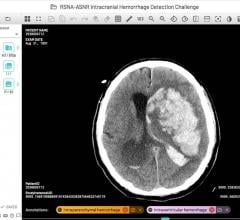

Pooja Rao, Ph.D., co-founder of Qure.AI and head of research and development for the company, explains how the company's ...

June 30, 2020 — Imaging Artificial Intelligence (AI) provider Qure.ai announced its first US FDA 510(k) clearance for ...